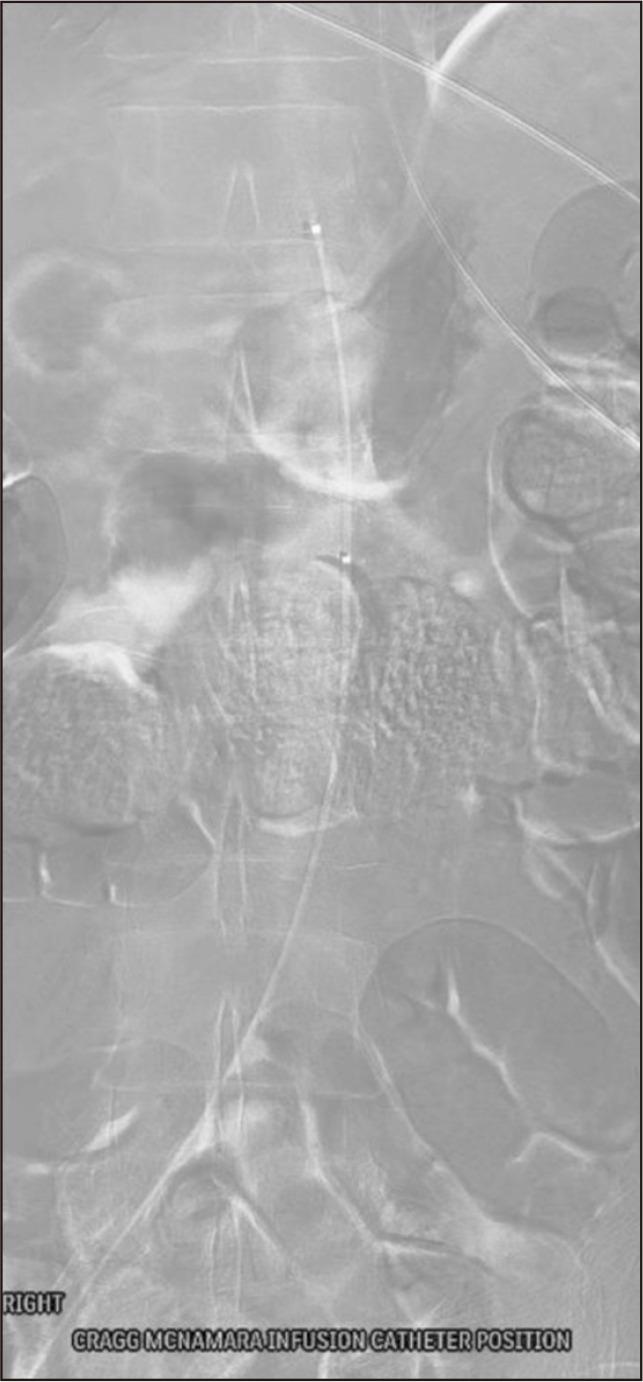

Spontaneous aortic thrombosis is exceedingly rare, and optimal treatment remains uncertain. We present an unusual case of a spontaneous aortic thrombus at the renal artery level in a patient undergoing active cisplatin treatment for urothelial carcinoma. Management included catheter-directed thrombolysis followed by thrombectomy. An open cutdown was performed on the left common femoral artery (CFA), with right groin access via a 6-Fr sheath. Clamping of the left superficial and deep femoral arteries, along with balloon occlusion of the right common iliac artery, prevented distal embolization. A Coda balloon introduced via direct left CFA puncture with a 20-Fr sheath was positioned above the aortic thrombus. After inflation, clots were trawled to the sheath, "sandwiching" the clots before removal of the balloon and sheath via the left groin. Post-operatively, the patient recovered well and received continued therapeutic anticoagulation.

自发性主动脉血栓形成极为罕见,最佳治疗方法仍不明确。我们报告了一例不寻常的病例,一名正在接受顺铂治疗尿路上皮癌的患者在肾动脉水平出现自发性主动脉血栓。治疗措施包括导管定向溶栓,随后进行血栓切除术。在左股总动脉(CFA)进行开放切开,通过一个6F鞘管进入右腹股沟。夹闭左股浅动脉和股深动脉,同时球囊封堵右髂总动脉,防止远端栓塞。通过直接经20F鞘管穿刺左CFA引入的Coda球囊置于主动脉血栓上方。球囊充气后,将血栓拖至鞘管,在通过左腹股沟移除球囊和鞘管之前对血栓进行“夹取”。术后,患者恢复良好,并继续接受抗凝治疗。